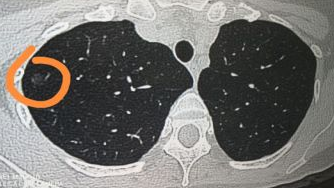

形状''古怪'':一般来说,良性肺部结节的形状比较规则,边界清晰。但是如果肺部结节的形状较为''古怪'',出现分叶、毛刺、胸膜牵拉、含气细支气管征和小泡征、偏心厚壁空洞等,需要当心是否是恶性结节。

发于右上肺:一般来说,恶性肿瘤好发于右上肺部,因此,此部位出现结节,需要进一步排除是不是恶性肿瘤。如果不在这个区域,那么恶性的可能性相对较小。